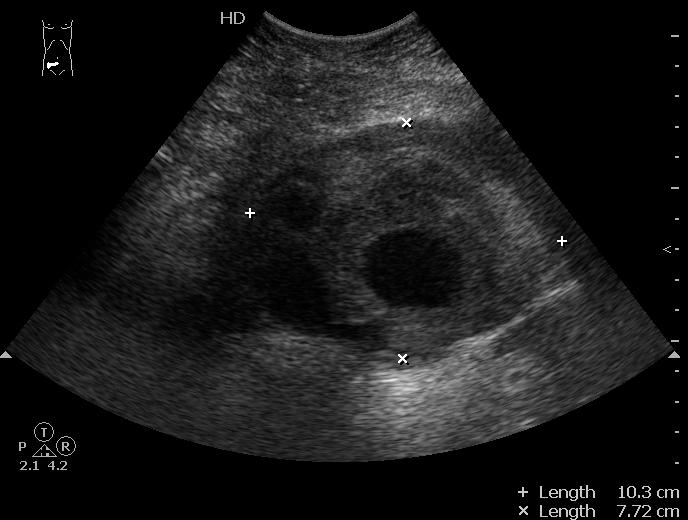

Разрыв аневризмы брюшного отдела аорты

Да, сегодня пришел своими ножками на контрольное исследование.

Ему выполнена резекция аневризмы, установлен "Y"-протез.